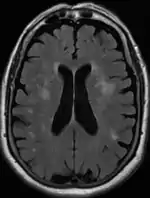

Leukoaraiosis is a particular abnormal change in appearance of white matter near the lateral ventricles. It is often seen in aged individuals, but sometimes in young adults.[1][2] On MRI, leukoaraiosis changes appear as white matter hyperintensities (WMHs) in T2 FLAIR images.[3][4] On CT scans, leukoaraiosis appears as hypodense periventricular white-matter lesions.[5]

These white matter changes are also commonly referred to as periventricular white matter disease, or white matter hyperintensities (WMH), due to their bright white appearance on T2 MRI scans. Many patients can have leukoaraiosis without any associated clinical abnormality. However, underlying vascular mechanisms are suspected to be the cause of the imaging findings. Hypertension, smoking, diabetes,[3] hyperhomocysteinemia, and heart diseases are all risk factors for leukoaraiosis.